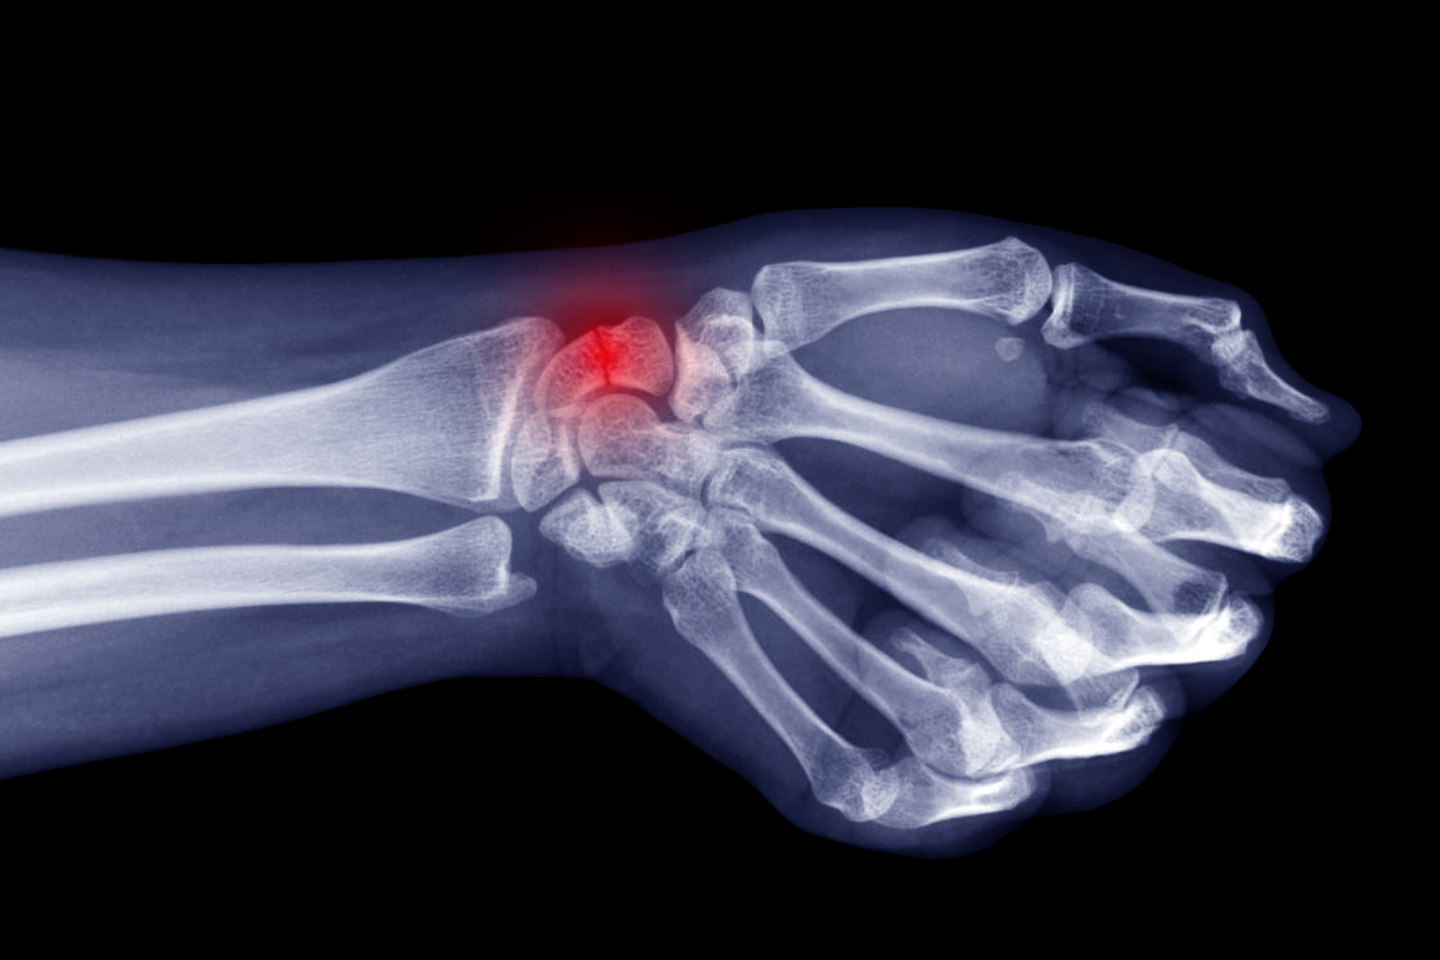

Wrist Scaphoid Nonunion